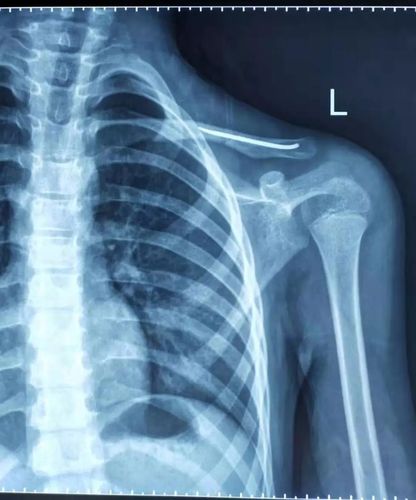

锁骨骨折有鼓包图片

锁骨骨折有鼓包图片,锁骨错位重叠长好图片

锁骨骨折

锁骨错位重叠长好图片

右肩锁骨骨折图片

锁骨骨折保守治疗图片

锁骨骨折错位愈合图片

锁骨骨折愈合凸起图片

锁骨骨折畸形愈合图

锁骨骨折图片

锁骨骨折自然恢复图片

锁骨骨折愈合图片